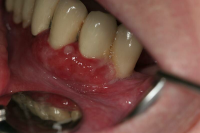

Akut inflammatorisk destruktiv sjukdom i gingiva och parodontium.

Karakteriseras av approximala nekrotiska och fibrintäckta sår (nedsmälta papiller) som är smärtsamma vid beröring och mycket lättblödande.

Patienten kan ha påverkat allmän tillstånd och ofta foeter ex ore.

I anamnesen förekommer ofta kombination av nedsatt immunförsvar, rökning, stress och dålig munhygien. HIV/Aids kan finnas som bakgrundsfaktor.

Nekrotiserande ulcerös gingivit: